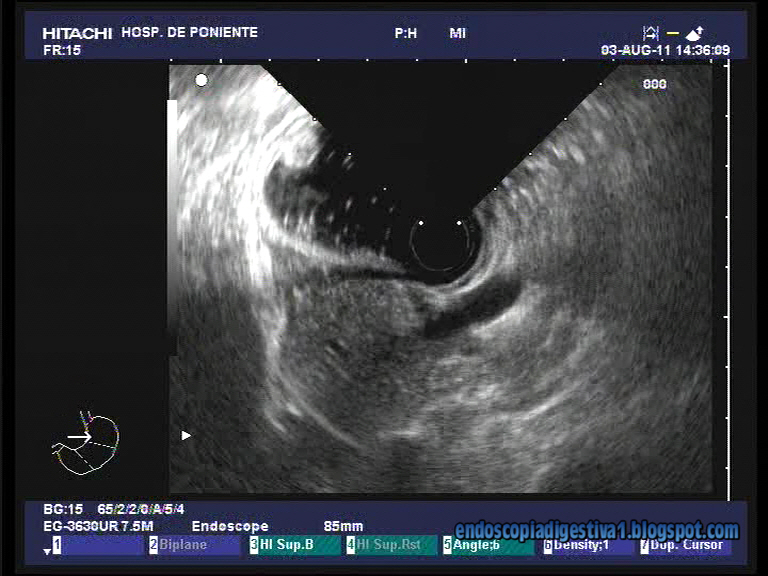

Dentro de las lesiones subepiteliales del tubo digestivo, una de las mas comunes en el tramo digestivo superior, es el lipoma. Frecuentemente son asintomáticos y de crecimiento lento, aunque en ocasiones (cuando son grandes y semipediculados), pueden ulcerarse y sangrar o provocar una obstruccíon en la salida gástrica por intususcepción en localización pilórica o bulbar. Generalmente no requeiren tratamiento, salvo que sean de gran tamaño. Se pueden extirpar endoscópicamente con la técnica de «let and go» usando endoloops. Los de tamaños muy grandes (> 5 cm) requeiren tratamiento quirúrgico. La imagen endoscópica suele ser muy sugerente debido al color amarillento de la lesión y el signo de la almohada cunado se le presiona con un fórceps de biopsia. La ecoendoscopia radial sin necesidad de punción confirma el diagnóstico en la mayoría de los casos. Son lesiones hiperecogénicas, regulares y ovoideas, dependientes de la submucosa (3ª capa a 7.5 Mhz). Se expone el caso de un lipoma gástrico de 1 cm, localizado en el cuerpo gástrico, hacia la cara anterior, de una paciente de 45 años de edad al realizarle una gastroscopia por molestias dispépticas.